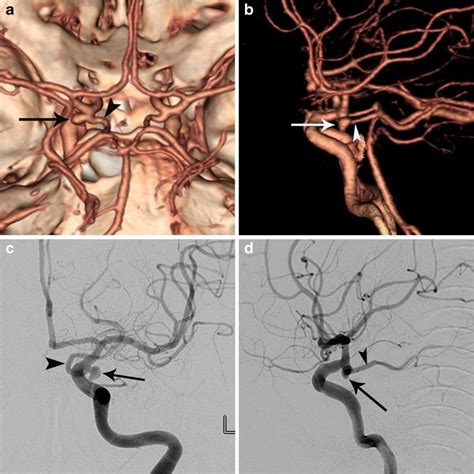

Imaging and Diagnostic Approaches

To visualize the Posterior Communicating Artery and assess its patency or detect potential pathology, clinicians rely on advanced neuroimaging techniques. Modern diagnostics allow for a detailed view of the cerebrovascular anatomy without the need for invasive procedures in many cases.

Common imaging modalities include:

• Magnetic Resonance Angiography (MRA): A non-invasive method using magnetic fields to create detailed images of the brain's blood vessels.

• Computed Tomography Angiography (CTA): Uses intravenous contrast and high-speed CT scans to provide precise mapping of the arterial flow.

• Digital Subtraction Angiography (DSA): Considered the gold standard, this invasive procedure involves injecting contrast dye directly into the arteries to provide the highest resolution images of the PCoA and its branches.